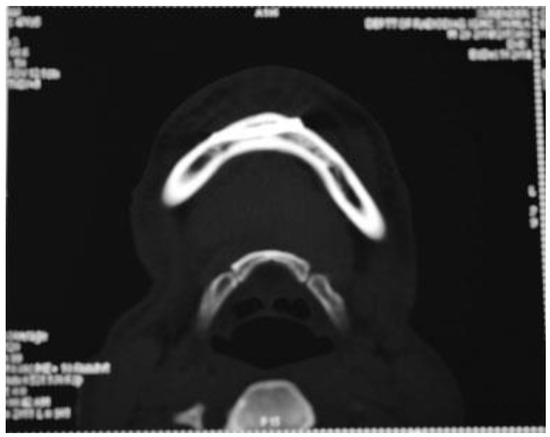

Figure 6. Case 1: Preoperative CT scan of axial section showing interforaminal fracture of right side mandible.